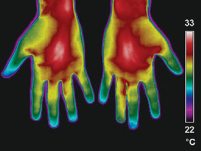

La neuropatía de fibra fina es causa de dolor, hormigueos, síntomas disautonómicos, fatiga/cansancio, etc., que se manifiestan en numerosas enfermedades como la Fibromialgia, el síndrome de Fatiga Crónica (Encefalitis Miálgica), el Covid persistente, la enfermedad de Parkinson o la Diabetes, por mencionar varios ejemplos.

Las ventajas de esta técnica se basan en su precisión y en que es una técnica no invasiva a diferencia de las biopsias cutáneas. Permite ver de una forma cuantificable la afectación de estas fibras nerviosas en pacientes con estas patologías en el que las técnicas neurofisiológicas convencionales suelen ser normales.